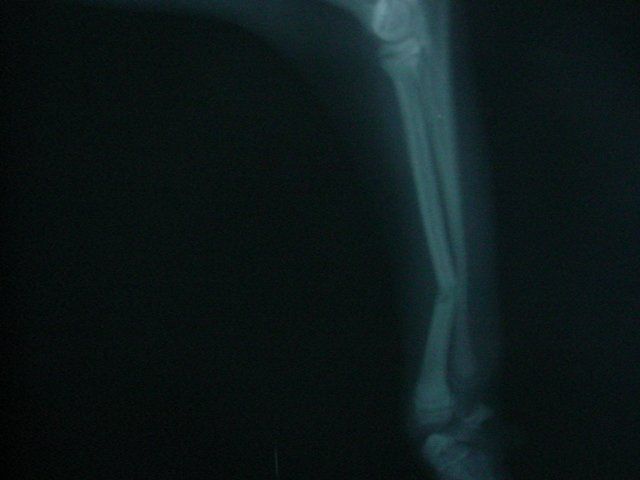

Dogs and cats commonly experience fractures secondary to trauma. The most common cause of the trauma is being hit by a car. Other trauma such as falls from furniture, jumping on unstable surfaces, leaping from a person's arms, etc. can also result in fractures. Below are some x-rays of some of the fractures we have seen at All Pets and their surgical correction using pins, plates, screws, and/or wires.